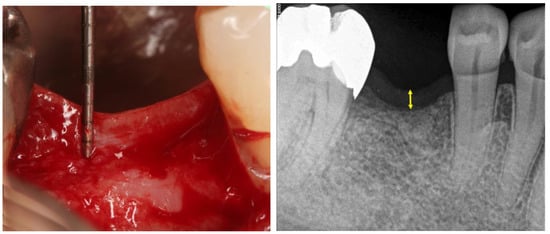

The analyses between the radiographic and clinical measurements showed similar values for the mucosal thickness, no presenting statistical differences (p = 0.634), with a mean and standard deviation of 2.26 ± 0.72 and 2.34 ± 1.27, for clinical and radiographic measurements, respectively. The Figure 3 show a box plots graph to compare the measured values and the Figure 4 shows the clinical and radiographic representative image of these measurements.

Figure 4.

Representative clinical image of the mucosal thickness measurement after the mucosal flap and a periapical x-ray image of the mucosal measurement.